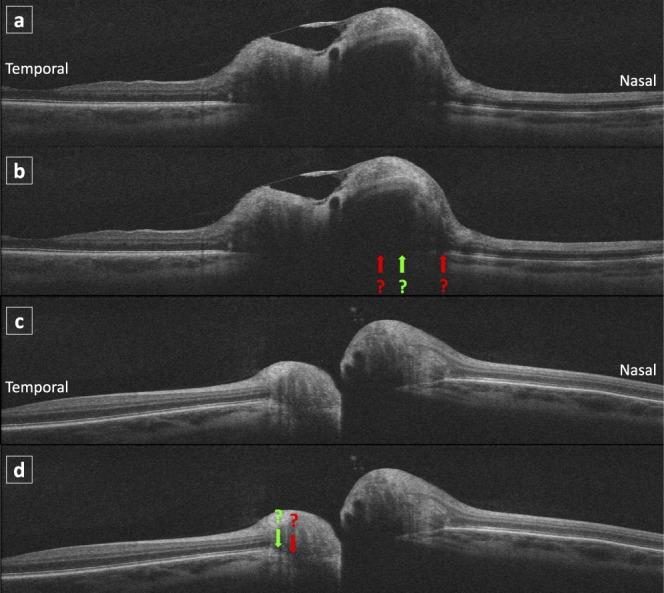

Recent studies indicate that the amount of deformation of the peripapillary retinal pigment epithelium and Bruch's membrane (pRPE/BM) toward or away from the vitreous may reflect acute changes in cerebrospinal fluid pressure. The study purpose is to determine if changes in optic-nerve-head (ONH) shape reflect a treatment effect (acetazolamide/placebo + weight management) using the optical coherence tomography (OCT) substudy of the Idiopathic Intracranial Hypertension Treatment Trial (IIHTT) at baseline, 3, and 6 months.

The pRPE/BM shape deformation was quantified and compared with ONH volume, peripapillary retinal nerve fiber layer (pRNFL), and total retinal (pTR) thicknesses in the acetazolamide group (39 subjects) and placebo group (31 subjects) at baseline, 3, and 6 months.

近期研究表明,视乳头周围视网膜色素上皮和布鲁赫膜(pRPE/BM)朝向或远离玻璃体的变形量可能反映脑脊液压力的急性变化。本研究的目的是利用特发性颅内高压治疗试验(IIHTT)的光学相干断层扫描(OCT)子研究,在基线、3个月和6个月时确定视神经乳头(ONH)形状的变化是否反映治疗效果(乙酰唑胺/安慰剂+体重管理)。

在基线、3个月和6个月时,对乙酰唑胺组(39名受试者)和安慰剂组(31名受试者)的pRPE/BM形状变形进行量化,并与ONH体积、视乳头周围视网膜神经纤维层(pRNFL)和视网膜总厚度(pTR)进行比较。